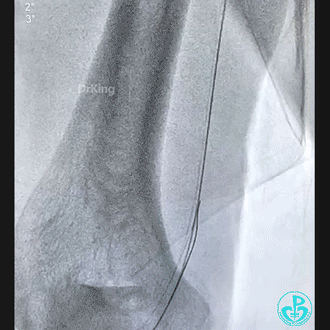

穿刺导丝掉进桡动脉,已经完全出了动脉鞘外。

先是从桡动脉鞘进抓捕器没有抓捕成功,后来从股动脉进抓捕器也没有抓捕成功。

桡动脉鞘进JR 4.0指引导管,送入Sion,沿Sion送入2.5mm球囊,球囊越过穿刺导丝到达远端,6atm“打起来”后回撤,导丝被球囊带回来到指引导管口附近。